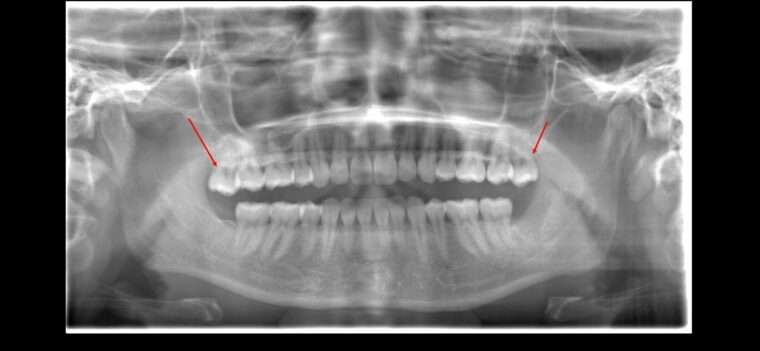

CASE 2

| 年齢・性別 | 30代・男性 |

| 主訴 | 左上下親知らず抜きたい |

| 抜歯期間 | 30分 |

| 抜歯費用 | 約2,500円(保険内) 別途CT撮影で3,000円 |

| 抜歯内容 | 左上下の親知らず抜歯 |

CASE 3

| 年齢・性別 | 20代・男性 |

| 主訴 | 左下親知らず抜きたい |

| 親知らずのはえ方 | 半埋伏 |

| 抜歯内容 | 左下の半埋伏親知らず抜歯 |